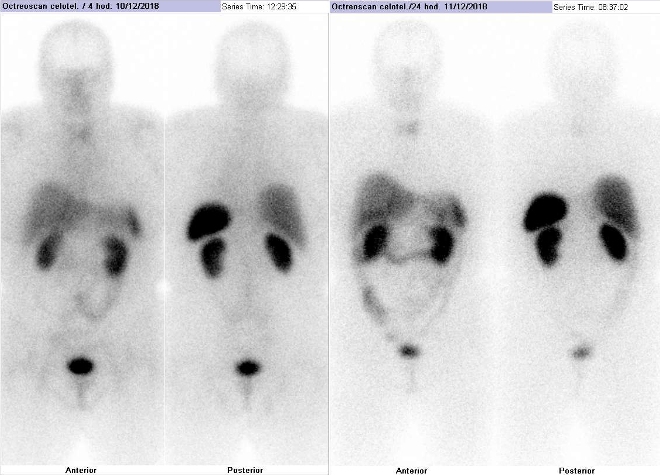

Scintigrafie Octreoscanem 12/2018:

Pomocí dvoudetektorové hybridní tomografické kamery Symbia T2 (SPECT/CT) firmy Siemens opatřené kolimátory pro střední energie jsme provedli celotělovou scintigrafii a také cílenou tomografickou scintigrafii (SPECT) a CT a fúzi obrazů SPECT/CT krku, hrudníku, břicha s pánví za 4, 24 a 48 hod. (obr. 1-4) po i.v. podání 190 MBq

analogu somatostatinu značeného 111In (přípravek OctreoScan firmy Mallinckrodt Medical).

/ Obr. č. 1: Celotělová scintigrafie v přední a zadní projekci. Vyšetření 4 a 24 hod. po aplikaci radioindikátoru.